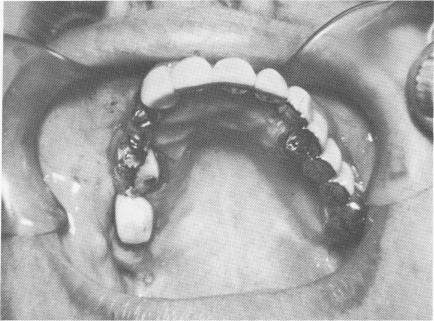

Using a template. When a triplant must be used in a long edentulous span, a template should be included in the restoration (Fig. 7-27) . This will pro-vide additional stability and brace the triplant against movements caused by the soft tissues pulling on its head. The template will rest on the soft tissues, be scalloped according to the crowns overlying them,

Fig. 7-27. A template is needed to supply additional stability. Triplants are to be used in the posterior regions and vent-plants in the anterior regions of this full arch template.

1 Triplant and vent plant endosseous implants in full arch template